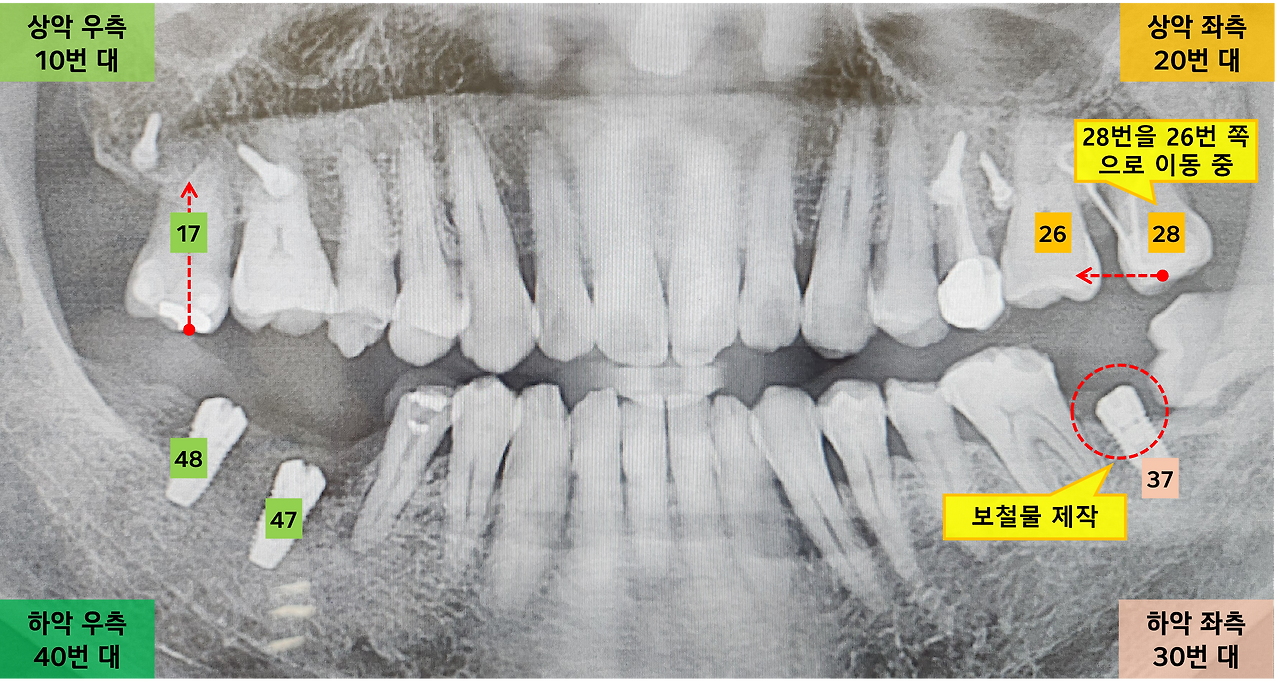

교정이 잘 진행되고 있습니다. 왼쪽 28번 치아의 이동이 거의 완료되어 마무리 단계로 접어들었습니다.

아래 사진 상으로는 좌측 28번과 26번 치아의 간격이 멀어 보이지만 예전에 찍었던 파노라마 사진에 표시한 것이고요. 실제로는 거의 좁혀져서 치간 칫솔이 들어가면 뻑뻑하다는 느낌이 들 정도로 좁아졌습니다.

교정 전문의는 왼쪽 28번 치아가 거의 자리를 잡은 것으로 보고, 37번 치아에 대한 임플란트 시술을 시작해도 되겠다는 판단을 한 것 같습니다. 위아래 치아가 거의 정렬이 된 것으로 보이니까요.